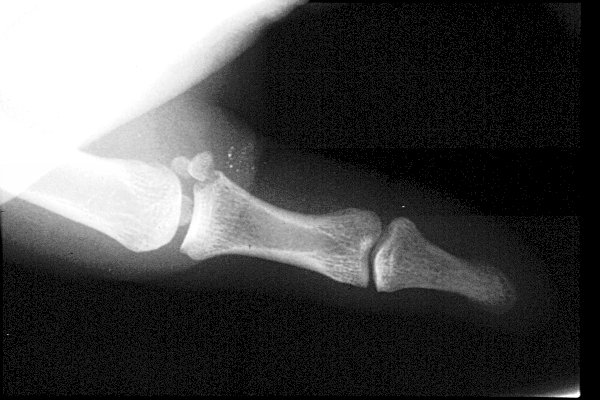

Return to Gamekeeper's Thumb